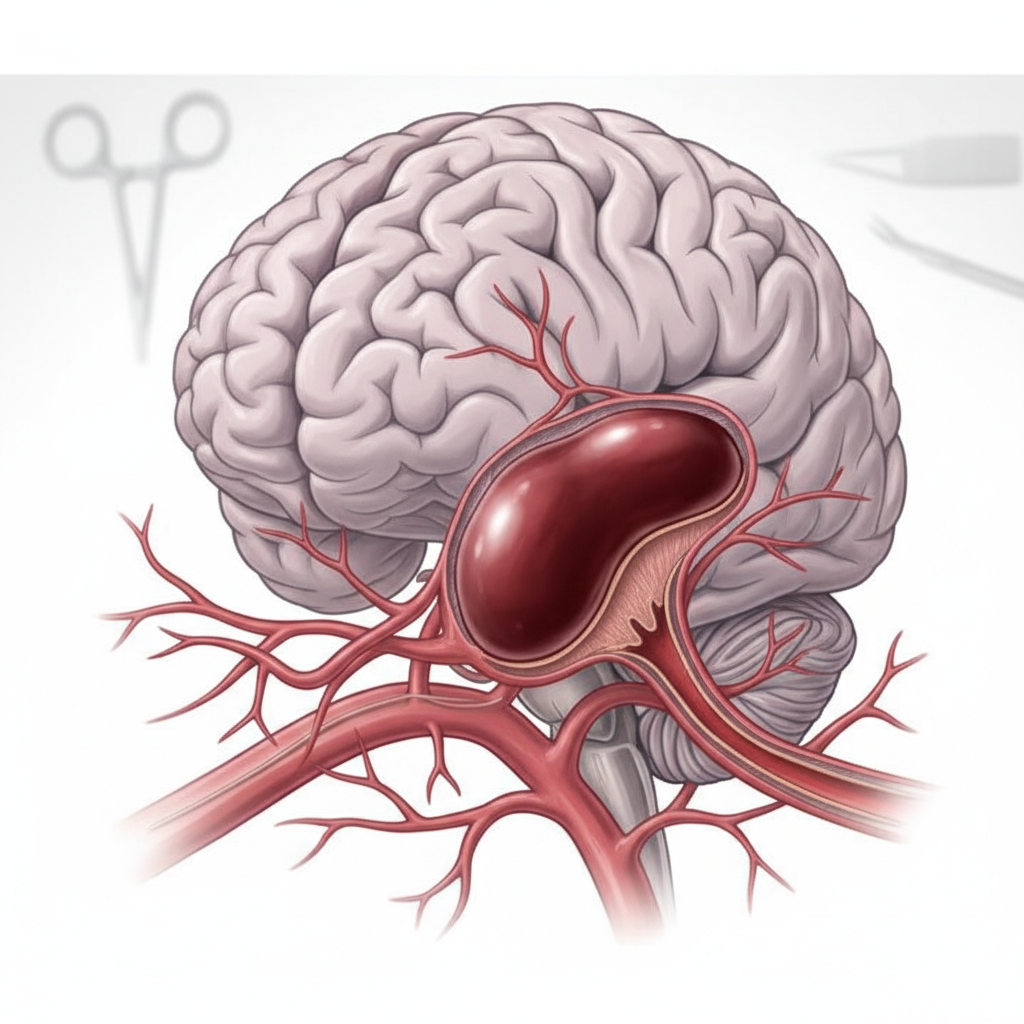

Descubra o que é aneurisma cerebral, seus riscos, sintomas e opções de tratamento. Saiba quando procurar um neurocirurgião em Brasília e por que o diagnóstico precoce salva vidas. Introdução O aneurisma cerebral é uma condição médica séria que afeta centenas de milhares de pessoas em todo o mundo, frequentemente sem que o paciente sequer saiba…

Descubra os principais mitos sobre aneurisma cerebral, sintomas, riscos e tratamentos neurológicos modernos e seguros.